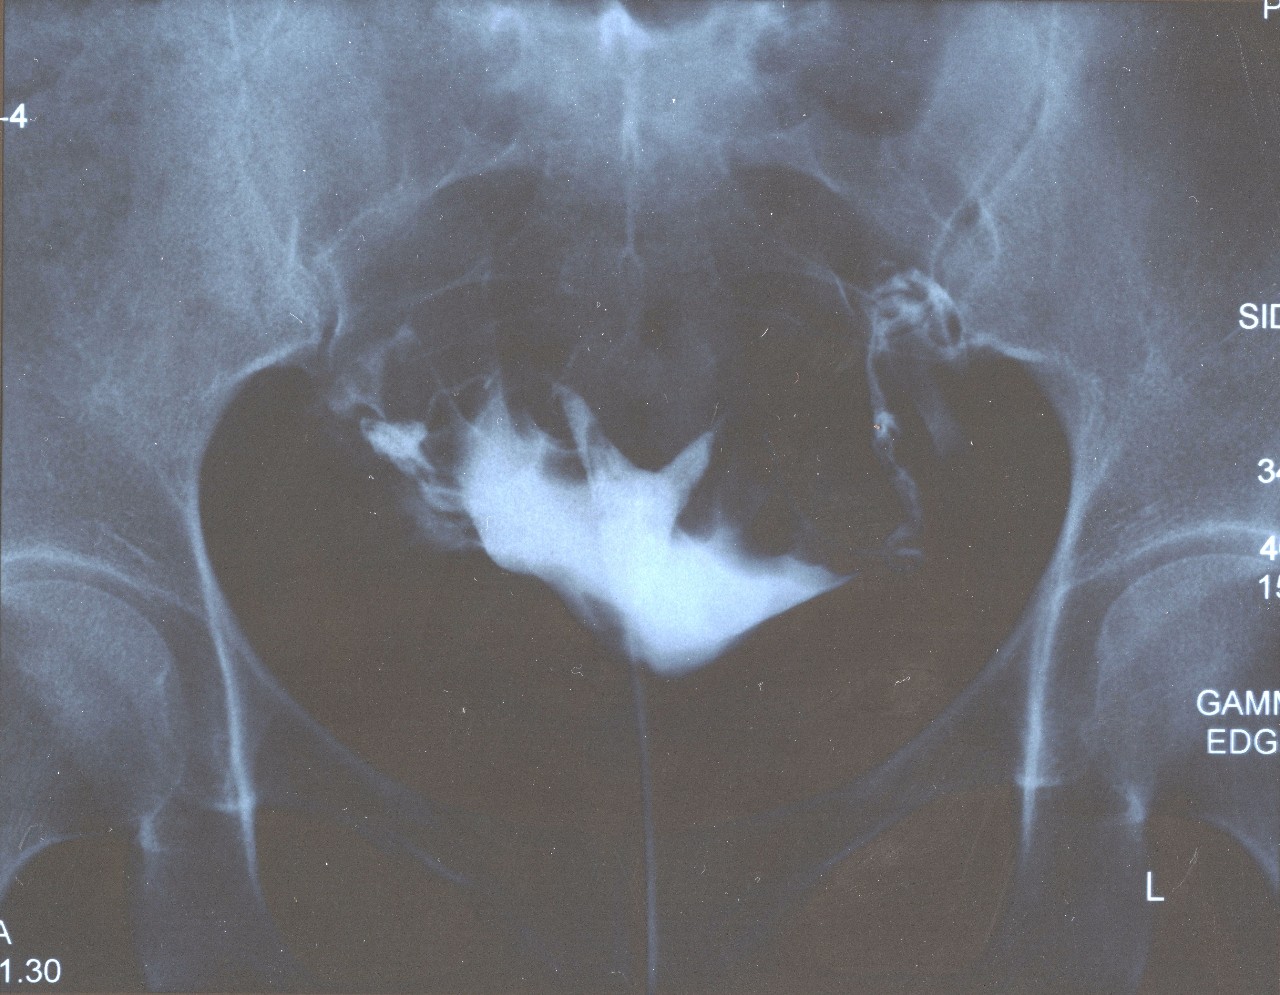

Медицинские снимки: Проходимость маточных труб

Раздел: Кадры-подсказки